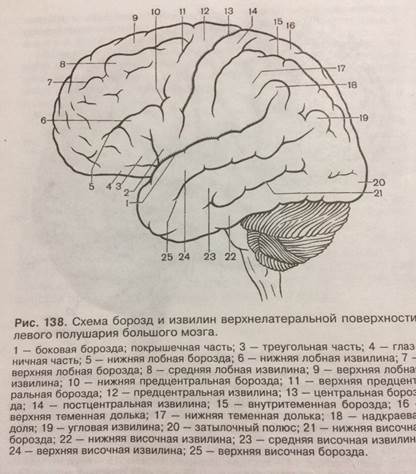

Анатомические снимки верхнелатеральной поверхности головного мозга